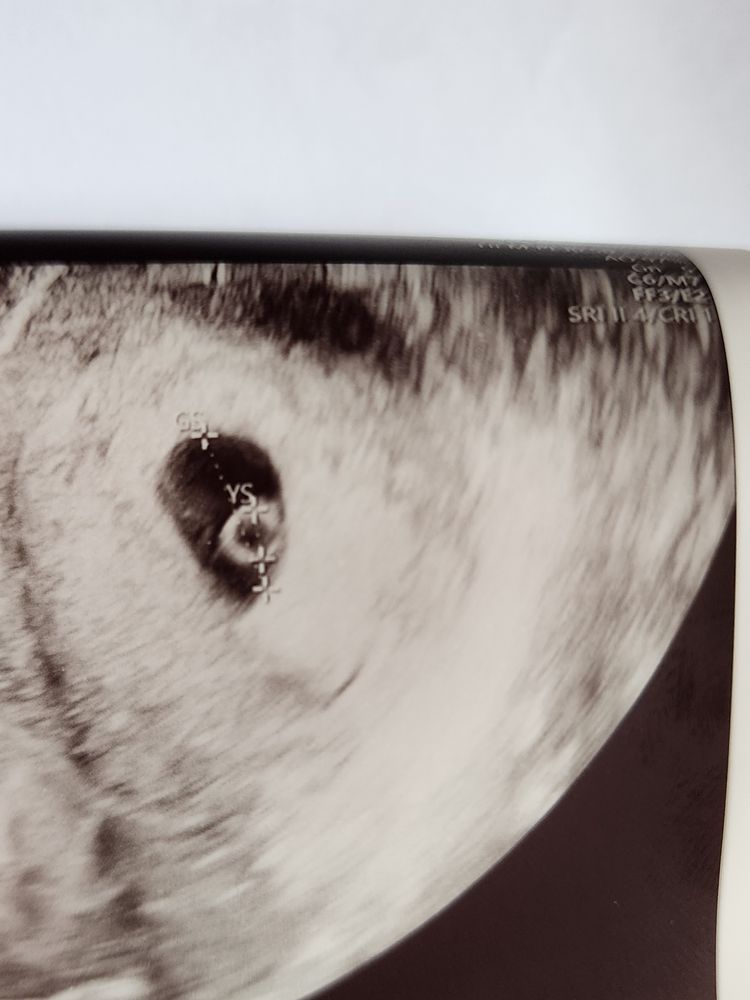

сходила на УЗИ, ПЯ 15мм, эмбриона пока не видно

Снова неделя неизвестности! Сходила на очередное УЗИ (первое было 10 дней назад, там было видно ПЯ 4мм), срок 6+3 по подтвержденной овуляции, ЖМ 4,5мм, эмбриона пока не видно.

Но вообще я щас глянула сама фото с УЗИ, и какое-то утолщение на краю мешочка виднеется! Так что возможно там есть эмбрион, просто ещё слишком мелкий для измерения